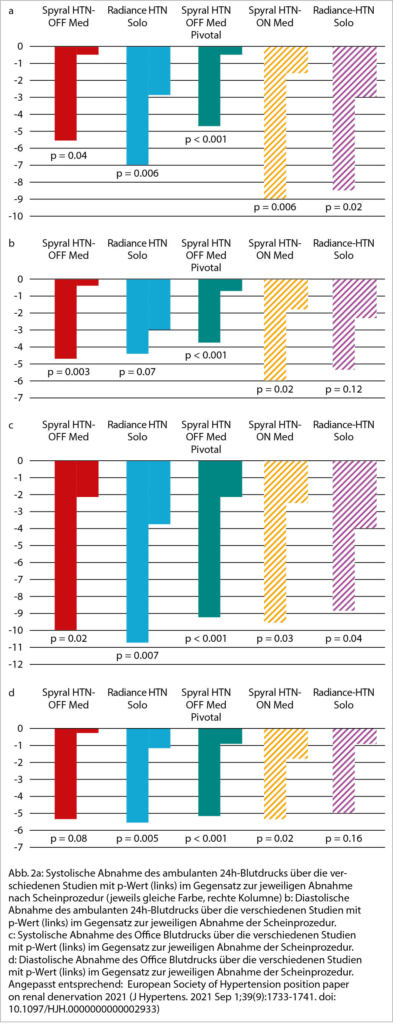

Die neuen Katheter und Interventionstechniken der beiden wichtigsten Katheterplattformen (Radiofrequanzablation von Medtronic oder Ultraschallablation von ReCor Medical) wurden in den letzten Jahren über mehrere Studien hinweg bei Patienten mit und ohne Medikation hinsichtlich der Blutdruckwirkung und der Sicherheit studiert. Hier zeigte sich ein konsistentes Bild mit einer systolischen Blutdrucksenkung von 5-10mmHg in der ambulanten 24-Stundenblutdruckmessung (ABPM) und 9-10mmHg in der Praxisblutdruckmessung (OBPM) über die einzelnen Studien hinweg. Diastolisch waren es 4-6 mmHg im ABPM und 5 mmHg im OBPM (Abb. 2 a-d).

Die Daten zur Sicherheit sind auch nach Anpassung der Interventionstechnik günstig: Abgesehen von wenigen Komplikationen am femoralen Zugangsweg (Hämatom, Pseudoaneurysma) sind keine akuten unerwünschten Sicherheitsereignisse (z.B. akutes Nierenversagen, Dissektionen, Perforationen, Blutungen) in den neuen, sham-kontrollierten randomisierten, Studien beobachtet worden. Daher wird die renale Denervation als gut verträglicher endovaskulärer Eingriff mit einem günstigen Nutzen-Risiko Verhältnis angesehen. Somit lassen die Daten der Studien der 2. Generation (Spyral HTN-OFF Med, Spyral HTN OFF Med Pivotal, Spyral HTN ON Med, Radiance HTN Solo, Radiance HTN Trio) auf eine klinische Wiedereingliederung der renalen Denervation in die Hypertoniebehandlung hoffen.